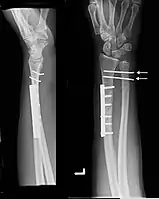

Images

-

Galeazzi fracture after surgical fixation